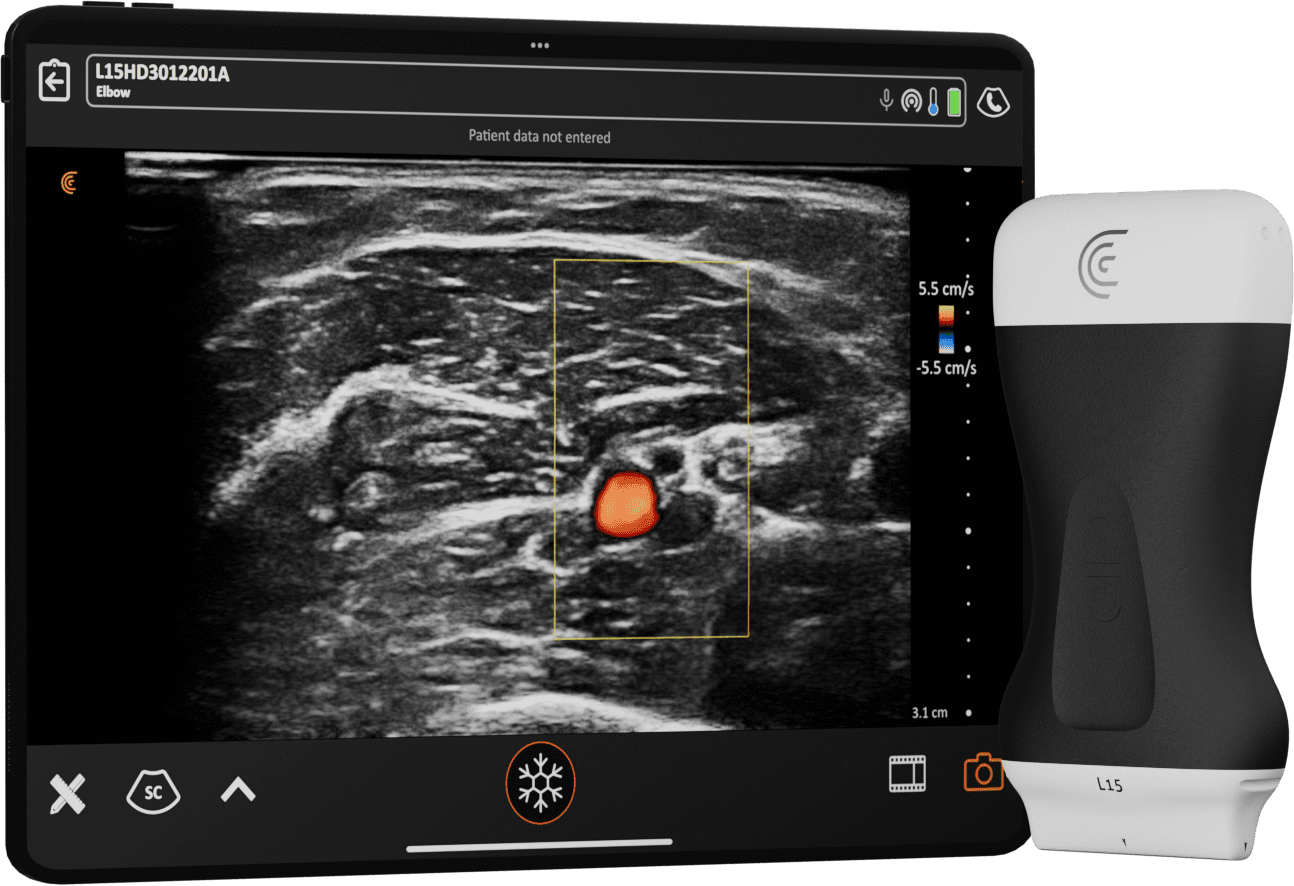

Images et

Intelligence à Emporter

Votre téléphone et Clarius sont tout ce dont vous avez besoin pour emporter la puissance de l'échographie partout où vous allez.